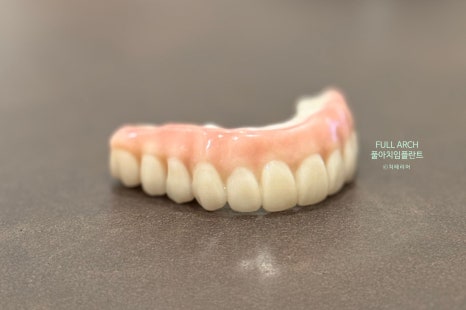

과도한 임플란트 없이 ALL ON X 로 턱뼈에 임플란트를 식립하는 방식으로 임플란트 개수는 6개 정도를 식립하여 하부구조를 단단하게 지지하게 수술한 뒤 풀 지르코니아로 만든 보철구조물을 올리는 치료방식이다.

최종 풀지르코이나 보철 구조물 *디오나비정품모델사진

보철의 모양은 마치 틀니 처럼 생겼으나 하부구조물에 단단하게 연결된 강한 고정형식의 임플란트 틀니의 업그레이드 버전이라고 말할 수 있다.

최종 보철물은 풀 지르코니아로 되어 있으며 최적의 보철 기능과 강도 및 심미적인 부분까지 해결할 수 있도록 연결한다.